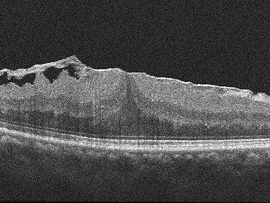

수술 후대학병원에서 오랜 기간 수많은 환자들을 진료하고 수술한 경험과 학술적 지식을 바탕으로 최선의 판단을 도와드리고,

수술 전후 체계적인 맞춤 관리를 통해 망막전막 환자분들의 시력과 삶의 질을 지켜드리고 있습니다.